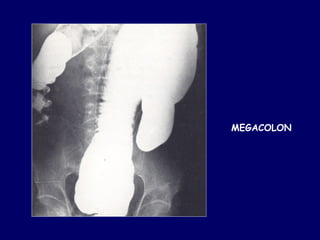

MEGACOLON

CHAGASICO

FASE CRONICA: 10 años o más de la primoinfección

Compromiso del tubo digestivo

Esófago y colon elongados y dilatados

Importante hipertrofia capa muscular

“MEGAS” digestivos